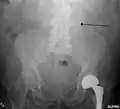

An abdominal aortic aneurysm is usually diagnosed by physical exam, abdominal ultrasound, or CT scan. Plain abdominal radiographs may show the outline of an aneurysm when its walls are calcified. However, the outline will be visible by X-ray in less than half of all aneurysms. Ultrasonography is used to screen for aneurysms and to determine their size if present. Additionally, free peritoneal fluid can be detected. It is non-invasive and sensitive, but the presence of bowel gas or obesity may limit its usefulness.[30] CT scan has nearly 100% sensitivity for an aneurysm and is also useful in preoperative planning, detailing the anatomy and possibility for endovascular repair. In the case of suspected rupture, it can also reliably detect retroperitoneal fluid. Alternative less often used methods for visualization of an aneurysm include MRI and angiography.[31]

The faint outline of the calcified wall of an AAA as seen on a plain X-ray -